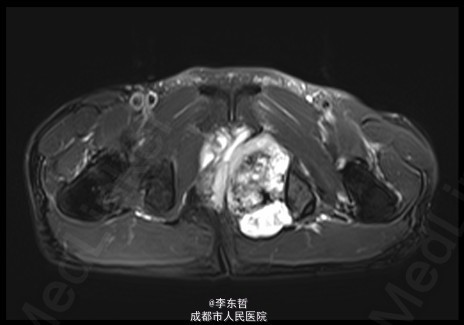

查体:臀部、会阴部、下腹部未触及包块,左下肢前内侧皮肤感觉较对侧减弱,双侧膝反射、跟腱反射正常引出,肛周皮肤感觉减退,直肠指检可触及质韧包块,活动度较差。双下肢肌力5级,双下肢各关节活动度可。 辅查:外院增强CT示:盆腔左侧壁见团块状软组织密度影,密度不均,其内见多发斑块高密度影,病灶大小约9.4*7.6cm,增强后强化不明确。我院X片示:左侧闭孔及耻骨区见不均匀高密度影,大小约6.2*6.7cm。我院MRI示:盆腔左份见长T1长T2肿块影,大小约10.3*7.7*10.5cm,向前推挤膀胱,向右推挤前列腺。我院骨扫描显示:耻骨联合及左侧耻骨支核素浓集。